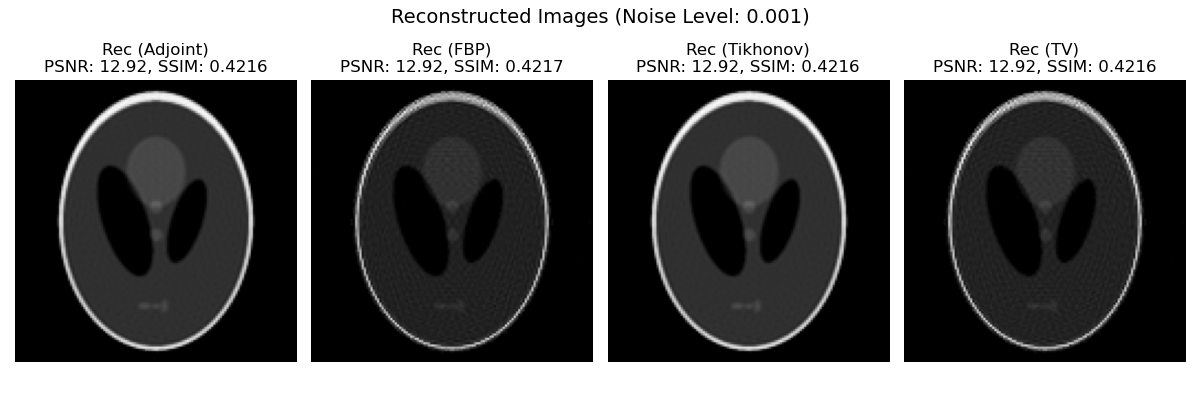

The primary objective of this subsection is to evaluate the reconstruction accuracy under varying noise levels using the discrepancy principle (5) as the stopping criterion. Similar to the investigation in [12] on various reconstruction operators for variational regularization, our iterative method also leverages a selection of initializers (excluding the NETT approach [45, 38]). Additionally, we introduce (the adjoint operator) as an initializer. This choice is particularly relevant as inherently satisfies Section 3.3, providing a fundamental, yet non-regularizing, starting point for the reconstruction. In Fig. 6, we present the true image of Shepp-Logan Phantom and noisy sinogram.

In the context of this model problem, Algorithm 1 is executed using noisy datasets at various noise levels. The resulting computational performance, including the required number of iterations and the achieved residual values, is summarized in Table 2. These findings suggest that all four initial reconstructors (Filtered Back Projection (FBP), Adjoint (Adj), Tikhonov (Tik) and Total Variation (TV)), when integrated with the IRMGL+ method, are capable of producing approximate solutions of comparable quality. To visually demonstrate the behavior of the discrepancy principle (5) as a termination rule for the proposed method, Fig. 8 displays the evolution of the residual with respect to the iteration count . This analysis is conducted for data with relative noise levels of , and , with iterations concluding upon satisfaction of the discrepancy principle or reaching a maximum of iterations.

As depicted in Fig. 7, we present the reconstructed images obtained at various noise levels for each of the four initial regularizers . It is noteworthy that, despite the IRMGL+ method demonstrating comparable performance and fast convergence across all initial reconstructors , initializations with and generally lead to superior results in the iterative process compared to others. The core issue arises from the fact that Filtered Backprojection (FBP) and Total Variation (TV) denoising are, by their nature, regularization methods. Consequently, when these are employed as initializers and then further processed by our proposed iterative regularization method, challenges such as over-regularization and a mismatch between regularization paradigms can emerge.